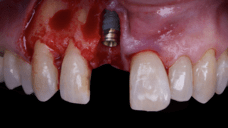

The main issue involved the upper right central incisor (tooth 1.1), which was devitalized and presented recurrent abscesses. Clinical and radiographic evaluation confirmed the presence of buccal bone wall resorption, leading to a significant defect in the alveolar ridge. This condition compromised both the hard tissue and the surrounding soft tissue, posing a challenge for achieving long-term stability and esthetic success in the anterior maxilla.

Due to the tooth’s location in the esthetic zone, the resorption and recurrent infections had a direct impact on the patient’s smile and overall confidence. She expressed dissatisfaction with the appearance of the affected tooth and emphasized the importance of restoring function and esthetics quickly. The clinical presentation highlighted the need for a treatment plan that combined immediate implant placement with simultaneous hard and soft tissue management to address the complex requirements of this case.

The surgical protocol began with the atraumatic extraction of tooth 1.1 to preserve as much of the alveolar socket as possible. Immediately following extraction, an N1 implant was placed into the socket using a guided surgical approach to ensure ideal three-dimensional positioning. The “one abutment one time” technique was applied to minimize soft tissue manipulation during the healing phase, which is particularly important in esthetic areas.